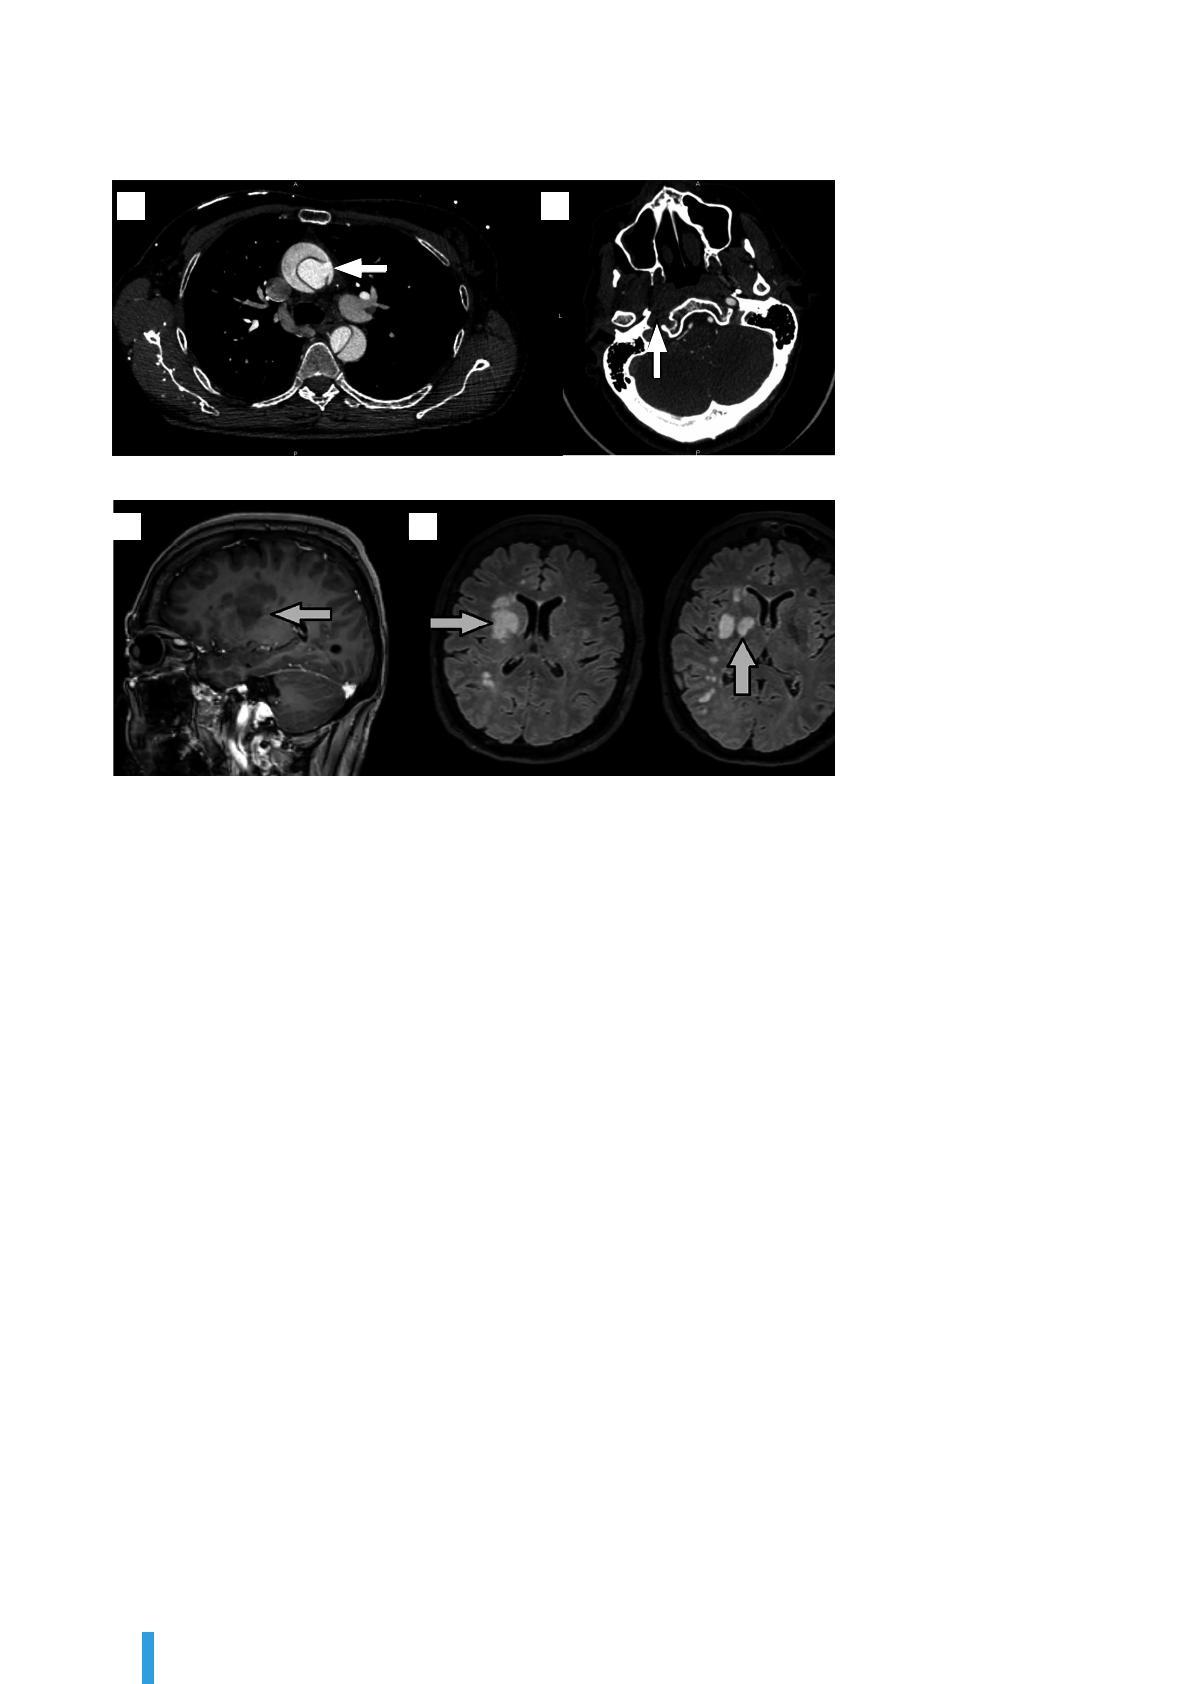

sans délai. En dehors d’une dissection des TSA, cet examen peut

être normal à la phase précoce. L’IRM cérébrale est plus sensible

que le scanner pour détecter une rupture de la barrière hémato-

encéphalique, mais sa faible disponibilité et la durée d’acquisition

limitent son indication en urgence chez des patients souvent ins-

tables sur le plan hémodynamique.